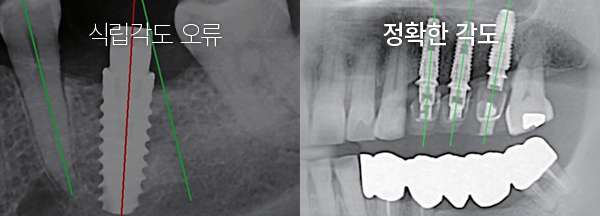

Á¤È®ÇÏ°í ¾ÈÀüÇÕ´Ï´Ù.

ÀÇ»çÀÇ °æÇè¿¡ ÀÇÇØ¼¸¸ ¼ö¼úÇÒ °æ¿ì, ½Ä¸³°¢µµ°¡ Ʋ¾îÁö´Â µî ÃÖÀûÀÇ À§Ä¡¿¡ ÀÓÇöõÆ®¸¦ ½Ä¸³Çϱâ Èûµç °æ¿ì°¡ ¸¹½À´Ï´Ù. ÄÄÇ»ÅÍ »ó¿¡¼ ¸ðÀǼö¼ú ÈÄ ÃÖÀûÀÇ ÀÓÇöõÆ® ½Ä¸³ À§Ä¡¸¦ °áÁ¤ ÇϹǷΠÁ¤È®ÇÏ°í ¾ÈÀüÇÏ°Ô ÀÓÇöõÆ®°¡ ½Ä¸³µË´Ï´Ù.